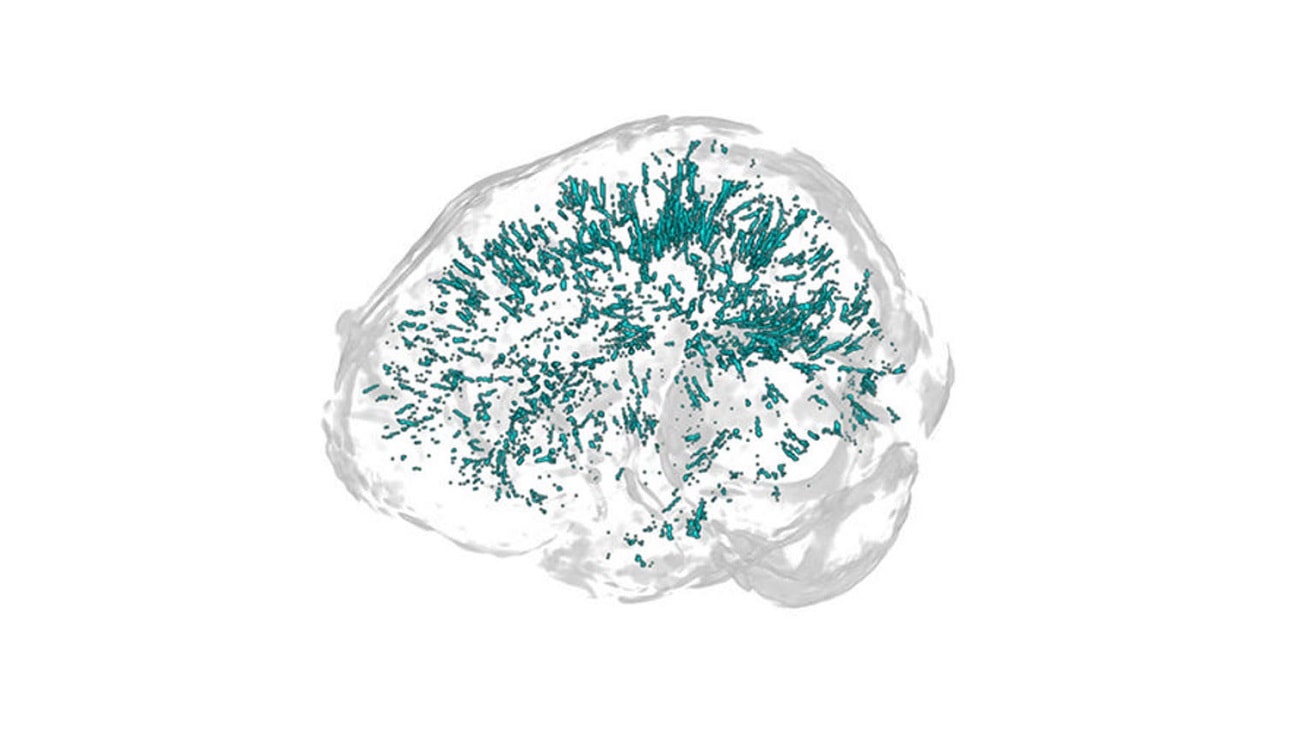

Przestrzenie okołonaczyniowe występują w centralnym regionie substancji białej mózgu bezpośrednio pod korą mózgową. Nie jest do końca jasne, za co odpowiadają, choć wiadomo, że powiększenie tych przestrzeni może zwiastować problemy.

Na obecną chwilę można się doszukiwać powiązań między funkcjonowaniem układu limfatycznego, a występowaniem bólów. Układ ten zajmuje się usuwaniem wszelkiego rodzaju odpadów z mózgu i układu nerwowego. Przestrzenie okołonaczyniowe biorą udział w tym procederze, co pozwala założyć, że jakaś forma nieprawidłowości przekłada się na występowanie migren.